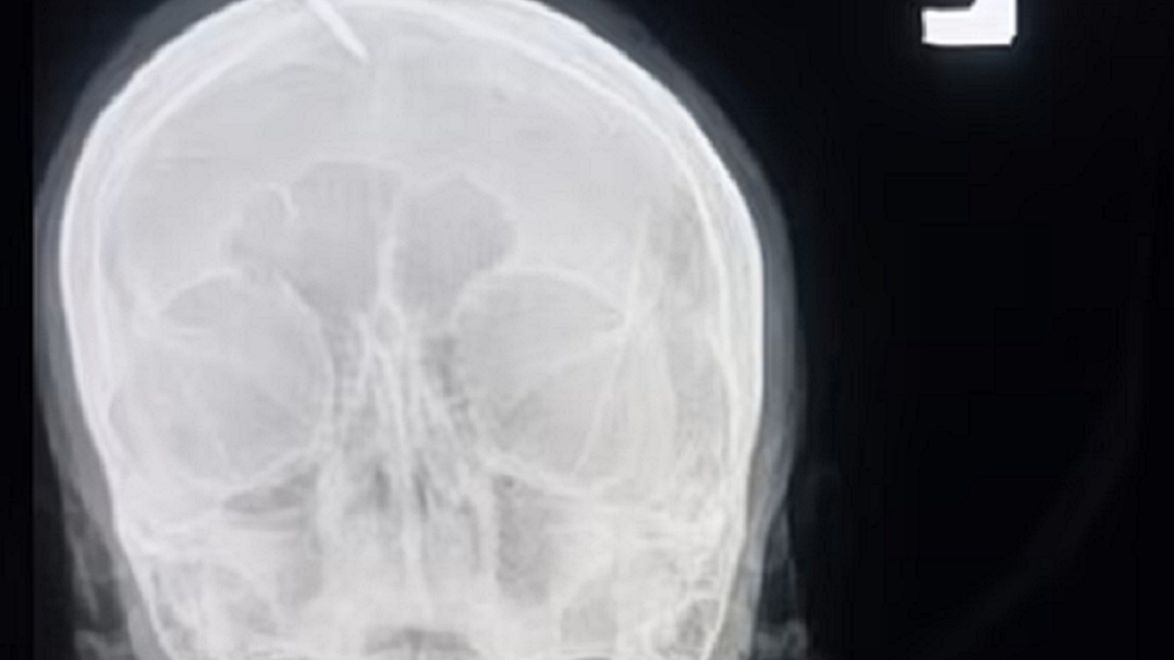

Ciężarna z Pakistanu zgłosiła się do szpitala z pięciocentymetrowym gwoździem wbitym w głowę. Kobieta powiedziała, że gwóźdź wbił jej uzdrowiciel zapewniający ją, że dzięki temu urodzi chłopca.

Kobieta ma w głowie gwóźdź, który miał zapewnić zmianę płci dziecka.Kobieta ma w głowie gwóźdź, który miał zapewnić zmianę płci dziecka. (Facebook)

Kobieta zgłosiła się do szpitala Lady Reading w mieście Peszawar w Pakistanie. W głowę miała wbity pięciocentymetrowy gwóźdź. Lekarzom powiedziała, że miejscowy uzdrowiciel zapewnił ją, że dzięki temu urodzi chłopca.

Komplikacje nastąpiły kiedy kobieta próbowała wyciągnąć gwóźdź. Ten był jednak bardzo mocno wbity w głowę. Lekarze, którzy zajęli się ciężarną powiedzieli, że bardzo cierpiała. Na szczęście nie doszło do żadnych poważnych komplikacji.